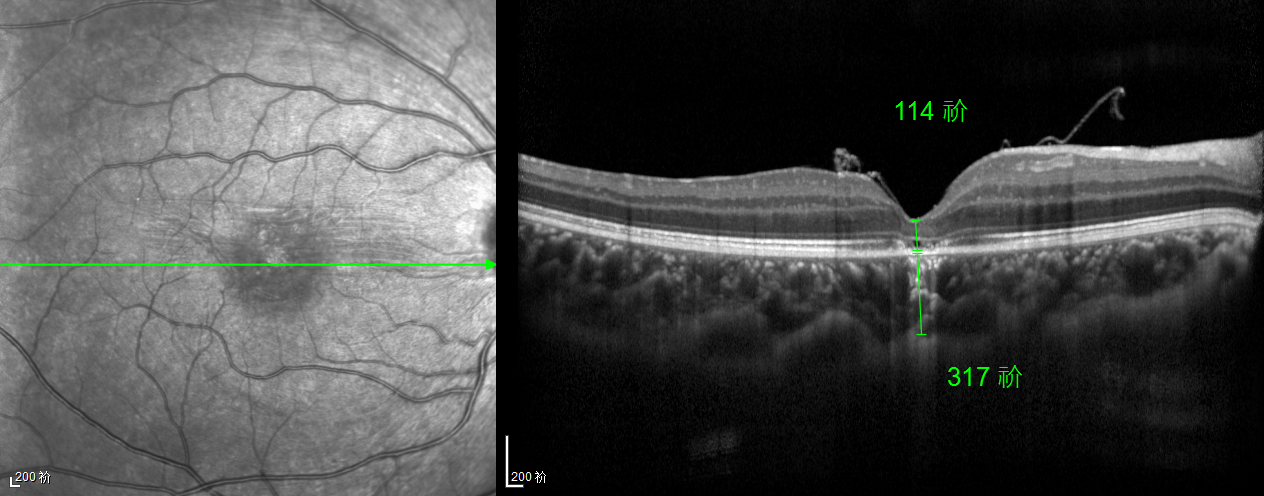

除此之外,利用自體組織覆蓋為黃斑裂孔提供了理想的愈合環(huán)境,裂孔閉合速度顯著快于傳統(tǒng)方法。誠誠接受手術(shù)24小時(shí)后,檢查可見內(nèi)界膜瓣位置良好;術(shù)后1個(gè)月,黃斑裂孔已經(jīng)閉合,視力恢復(fù)到0.5;術(shù)后兩個(gè)月,視力進(jìn)一步提升到0.7。

“書本的文字都變直了,黑板上的字也更清晰了!”

術(shù)后3個(gè)月復(fù)查時(shí),小男孩的眼睛閃耀著自信的光芒。